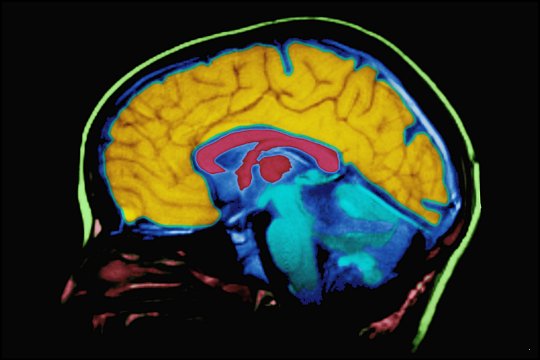

데자뷰가 일어나는 현상에 대한 또 다른 가설은 바로 신경세포가 정보전달에 있어 혼란을 일으키기 때문이라고 한다. 기억들이 정리되는 인간의 뇌에 있는 해마에서 혼란을 일으키는 것이다. 어떠한 원인으로 인하여 과거의 기억회로와 현재 경험하는 회로가 연결되게 되면 데자뷰와 같은 현상, 즉 기시감을 느끼게 된다는 가설도 있다.

MIT 공대 연구팀이 발표한 연구 보고서에 따르면, 기억을 담당하는 해마 중에서도 '해마치아이랑' 이라는 작은 부위에서 '삽화적 기억'을 담당하고 있다고 한다. 삽화적 기억이란 비슷하지만 다른 상황을 구별하는 기억을 말한다. 연구진은 이로써 데자뷰 현상이 뇌의 어느 부위에서 일어나는 지를 설명할 수 있게 되었다고 발표하였다.

해마는 장기 기억과 공간의 개념, 감정적인 행동을 조절하는 뇌의 일부로 관자엽의 안쪽에 위치하면서 변연계(둘레계통)에서 한가운데 원호의 일부를 차지하고 있다. 학습, 기억 및 새로운 것의 인식 등의 역할을 하면서 뇌활을 통하여 날섬유를 내보내기도 한다. 시상하부의 기능을 조절하는 역할을 하며 해마에 이상이 생겼을 때, 알츠하이머성 치매가 찾아오기도 한다.